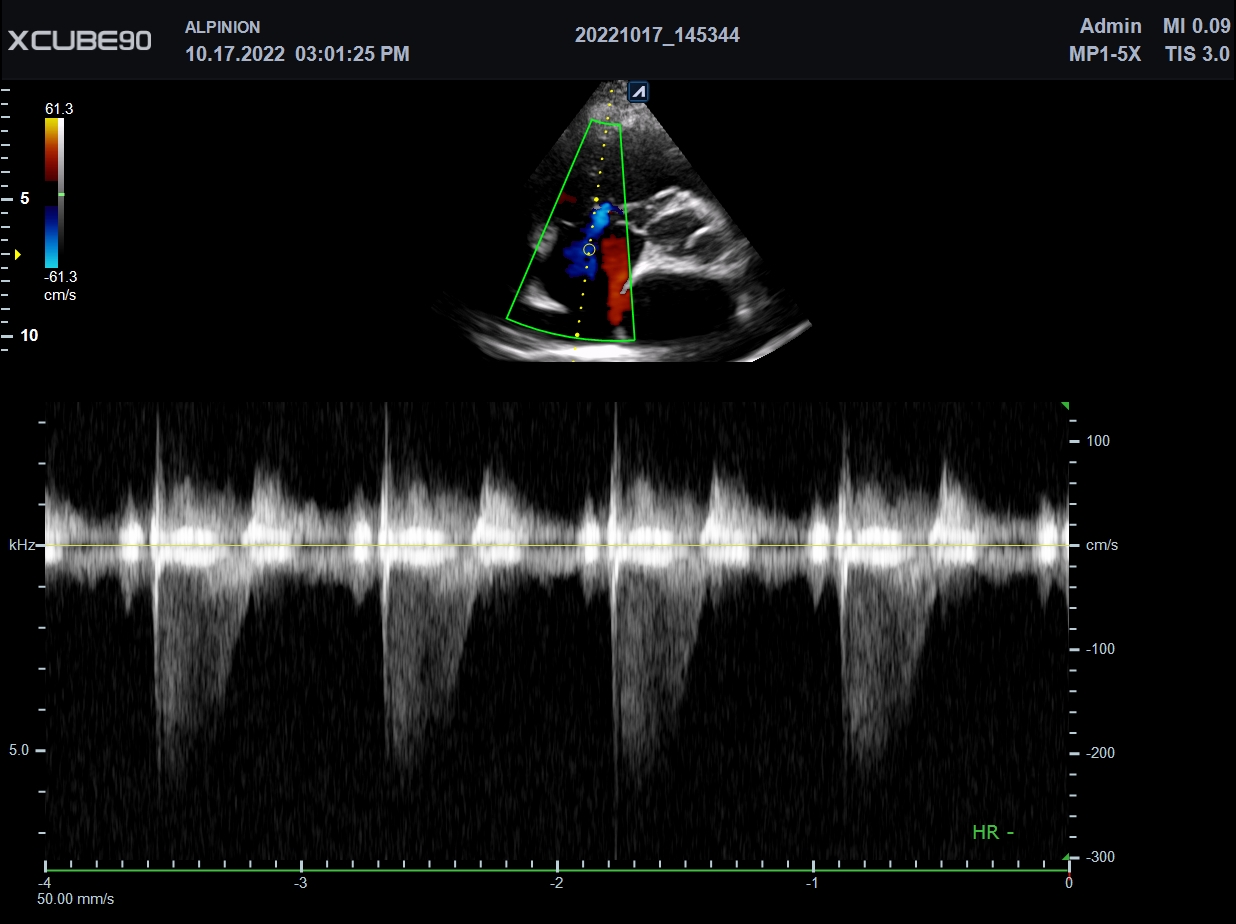

| Softwares Disponibles: | Shear Wave Elastography (SWE), Volume SRI, X+ pSWE (Point Shear Wave Elastography, X+ Assistant, X + Auto IVC, AutoEF, CEUS, X+Compare, Brilliant Flow, TIC Analysis, |

| Transductores: | Lineal 3~19MHz (256 cristales), Lineal 10~25MHz, Convexo 1~7MHz, Endocavitario 2~11MHz, Convexo Volumétrico 1~8MHz, Endocavitario Volumétrico 3~10MHz, Phased Array (alta resolución), TEE |